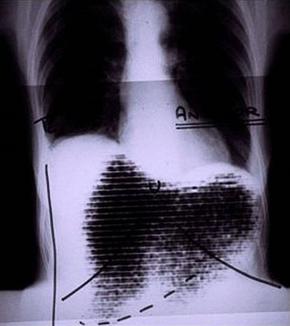

Rectilinear scan and chest X-ray fusion.png

Manual image fusion of x-rayed and rectilinear scanned chest